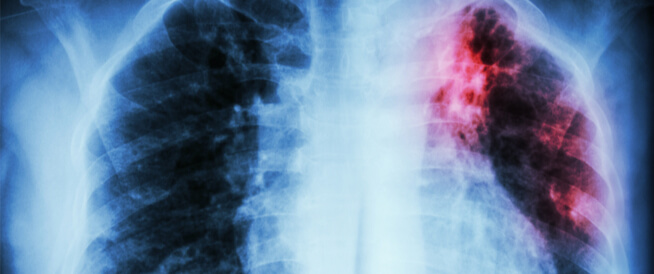

ما فترة علاج الدرن الرئوي؟.. الدرن الرئوي أو السل مرض بكتيري تتسبب فيه عصيات كوخ وهي بكتيريا مقاومة للادوية وللمضادات الحيوية، وهو مرض معدِ وينتقل عن طريق الرذاذ الذي يخرج من رئتي المريض.

ما فترة علاج الدرن الرئوي؟.. ويصيب الدرن عادة الاشخاص الذين يعيشون مع المريض أو الذين يجالسون المريض لمدة طويلة، وقد يصيب السل أعضاء أخرى من الجسم مثل الغدد اللمفاوية الغلاف الرئوي وغيرها.